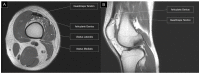

Elucidating its dynamic interaction within the knee joint, this exploration delves into the awareness regarding the articularis genus muscle for ultrasound-guided suprapatellar recess injections. While injections into the infrapatellar recess may proceed without ultrasound guidance, we highlight concerns regarding the potential cartilage injury. In contrast, especially with ultrasound guidance, suprapatellar recess injections significantly mitigate this risk, especially in the case of collapsed recess. Originating from the distal femur and vastus intermedius, the articularis genus muscle influences the tension of the suprapatellar recess during knee motion. Sonographically identifying this muscle involves visualizing the slender linear structure of the suprapatellar recess, with guidance on differentiation from the vastus intermedius. We provide a succinct approach to ultrasound-guided suprapatellar recess injections, emphasizing needle insertion techniques and strategies to prevent fluid accumulation. In conclusion, this study serves as a concise clinician's guide, underscoring the significance of the articularis genus muscle's sonoanatomy in ultrasound-guided suprapatellar recess injections. Ultimately, procedural precision and patient safety can be advanced in this aspect.